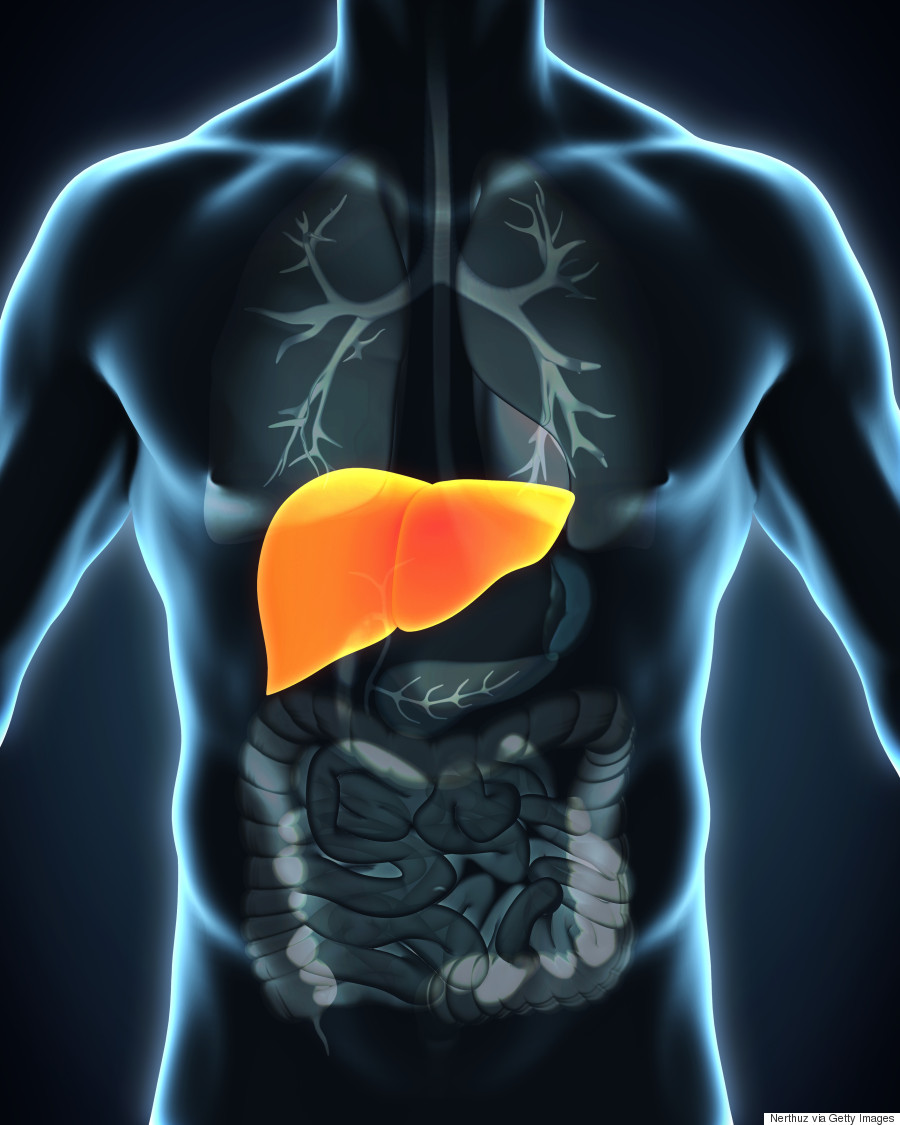

(1) Liver anatomy- The liver is located in the upper right-hand portion …